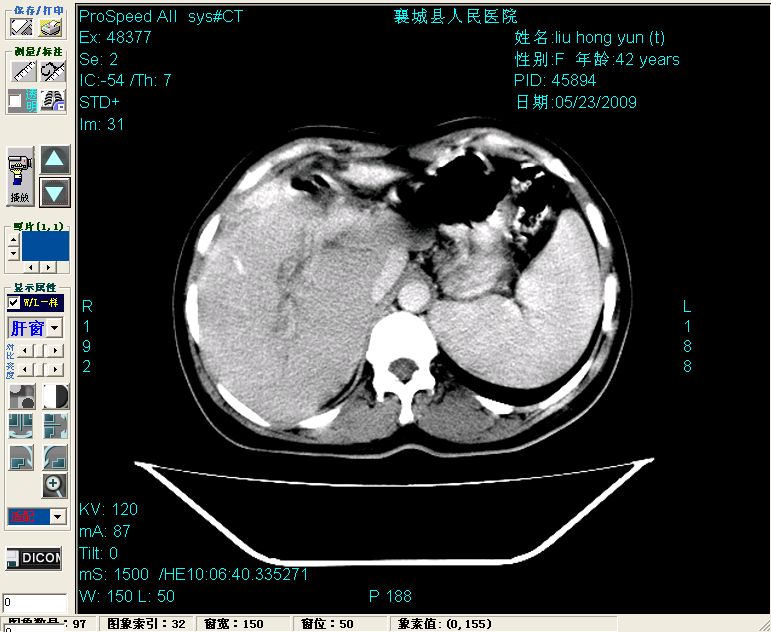

平扫:

平扫左肝外叶体积显著减小,左肝外叶见多房囊性低密度区,左肝实质及右肝前叶浅表实质呈低密度改变,左肝及右肝前叶胆管扩张,脾大